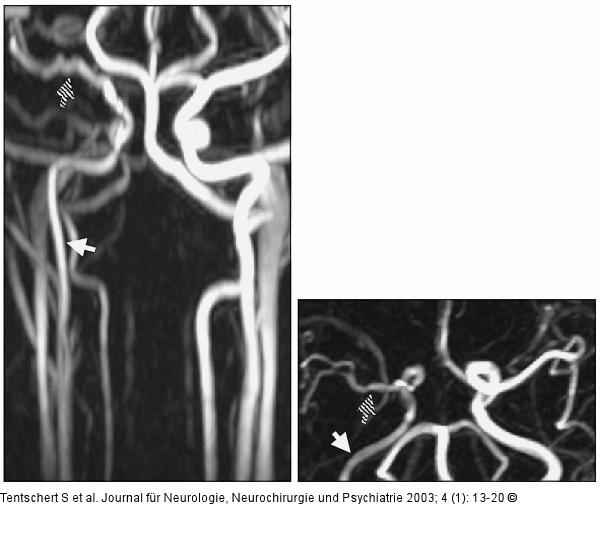

Abbildung 1: Arteria carotis - Perfusion MR-Angiographie (3D-PCA): Die perfundierten Gefäßlumina sind geschwindigkeitskodiert dargestellt. Die Arteria carotis dextra (weißer Pfeil) zeigt eine im Seitenvergleich moderate Flußverlangsamung im verschmälerten perfundierten Lumen. Auch die Arteria cerebri media dextra weist diesbezüglich deutliche, vergleichbare Veränderungen auf (schraffierter Pfeil). |

Abbildung 1: Arteria carotis - Perfusion

MR-Angiographie (3D-PCA): Die perfundierten Gefäßlumina sind geschwindigkeitskodiert dargestellt. Die Arteria carotis dextra (weißer Pfeil) zeigt eine im Seitenvergleich moderate Flußverlangsamung im verschmälerten perfundierten Lumen. Auch die Arteria cerebri media dextra weist diesbezüglich deutliche, vergleichbare Veränderungen auf (schraffierter Pfeil). |